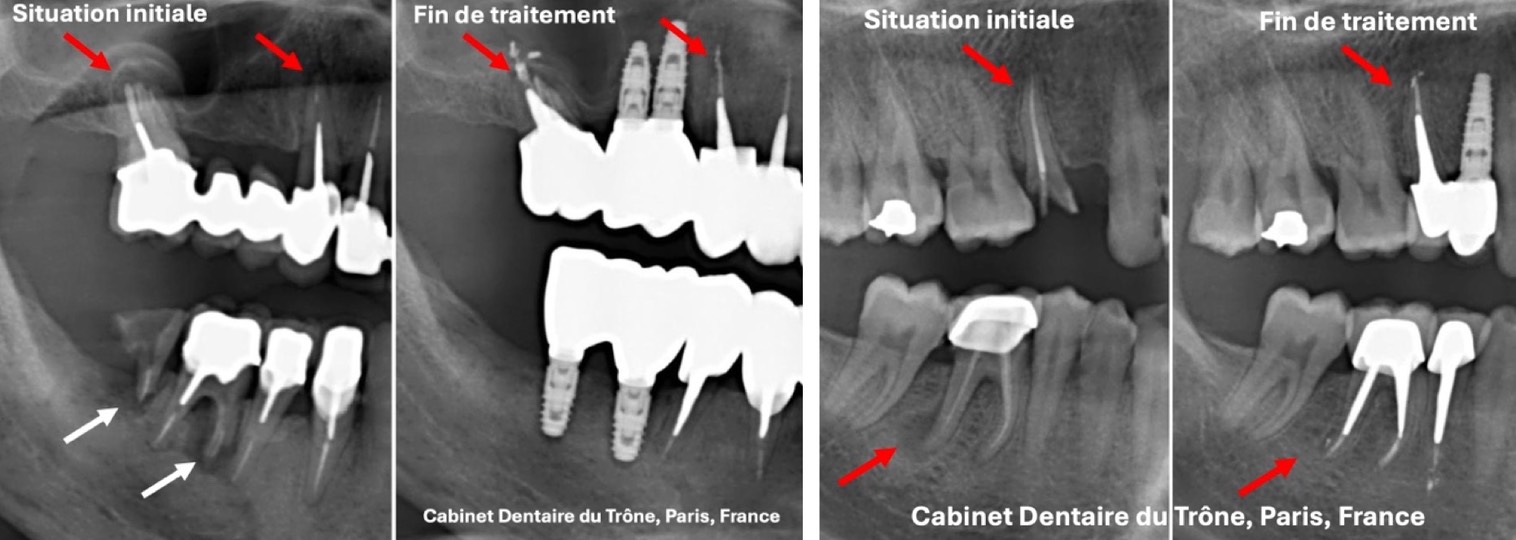

C’est la situation la plus fréquente et la plus complexe: une bouche présentant des dents absentes ou infectées à extraire, des dents cassées à sauver et de nombreux traitements anciens incomplets ou défectueux avec des kystes au bout des racines (flêches rouges ou blanches).

Le Cabinet proposera dans ces cas:

- l’élimination des dents infectées qui ne sont pas sauvables et leur remplacement par des implants (flêches blanches).

- le traitement des canaux infectés ou kystiques, puis l’assainissement des racines désinfectées et la reconstruction des dents délabrées. Au bout de quelques temps, les kystes au bout de dents vont régresser, voire disparaître (flêches rouges).